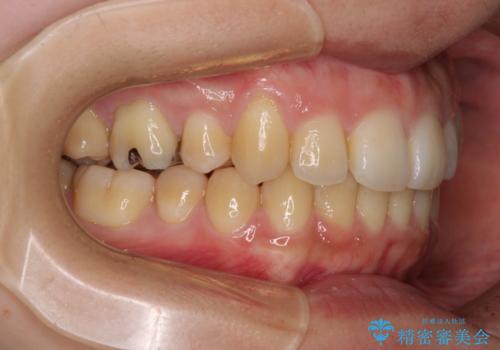

八重歯の抜歯矯正 補助装置を用いたインビザライン矯正

装着時間をしっかりと守ってくださったので、予定通りの期間で終了することができました。